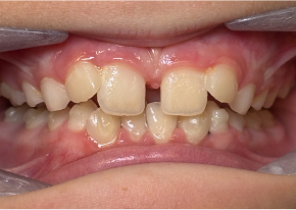

Report sul Caso 1

10 anni 0 mesi, 18 fasi di Invisalign Palatal Expander

Per gentile concessione della Dott.ssa Sandra Khong Tai

Pre espansione Invisalign Palatal Expander

Post espansione Invisalign Palatal Expander

Dopo il trattamento Invisalign First